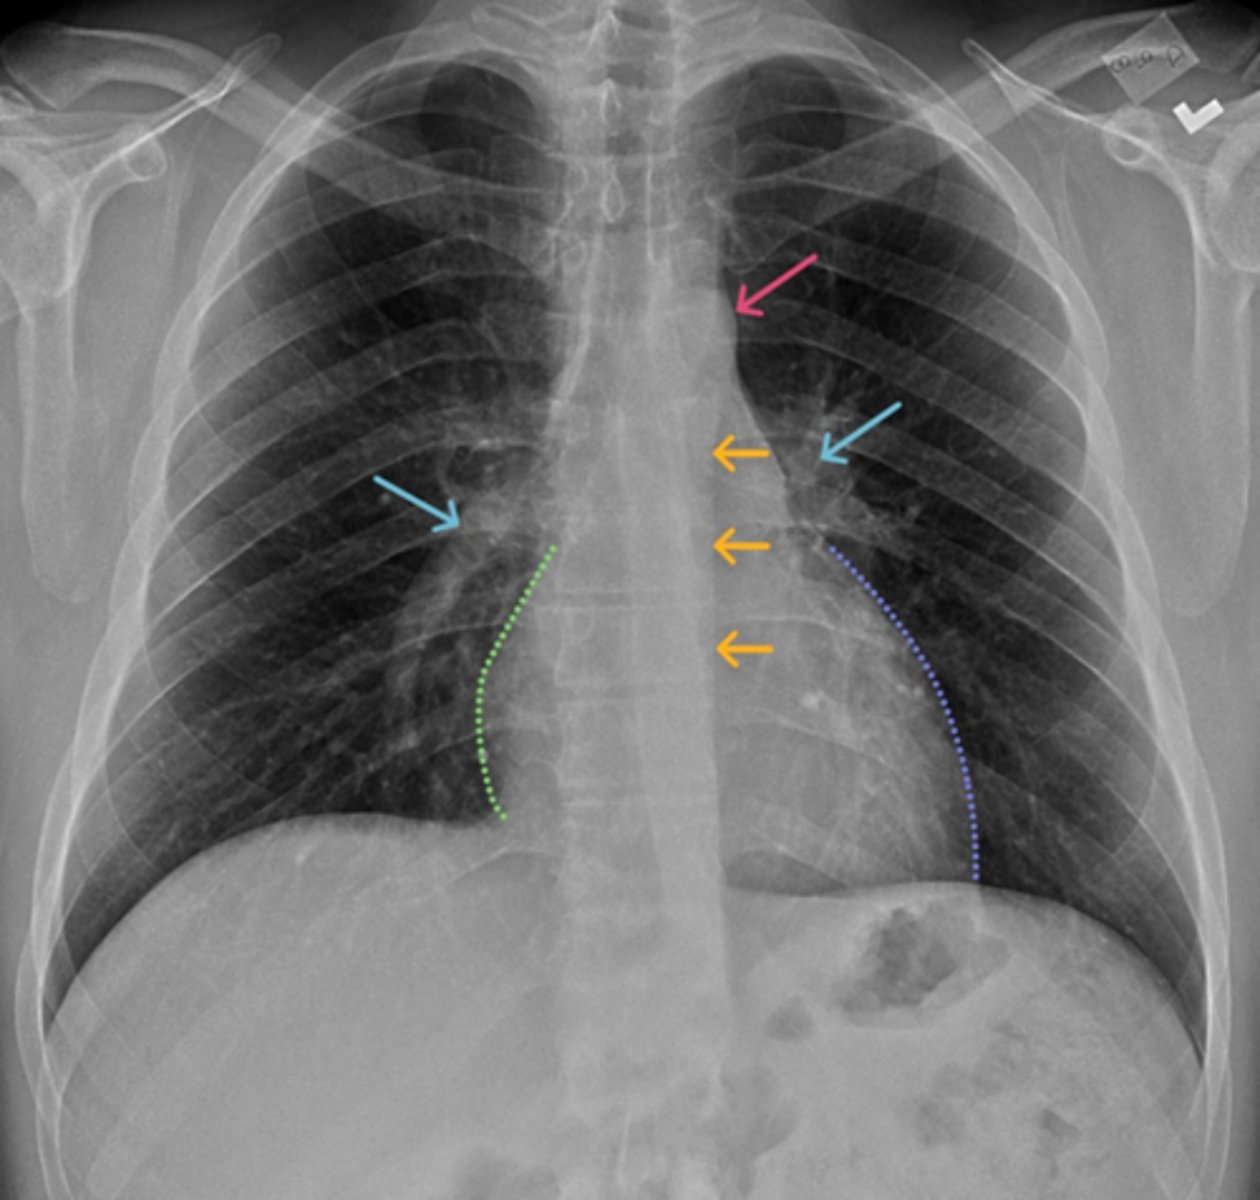

Aortic knob/arch

Pink Arrow

Left ventricle and border of the heart

Purple Line

Pulmonary arteries

Blue Arrows